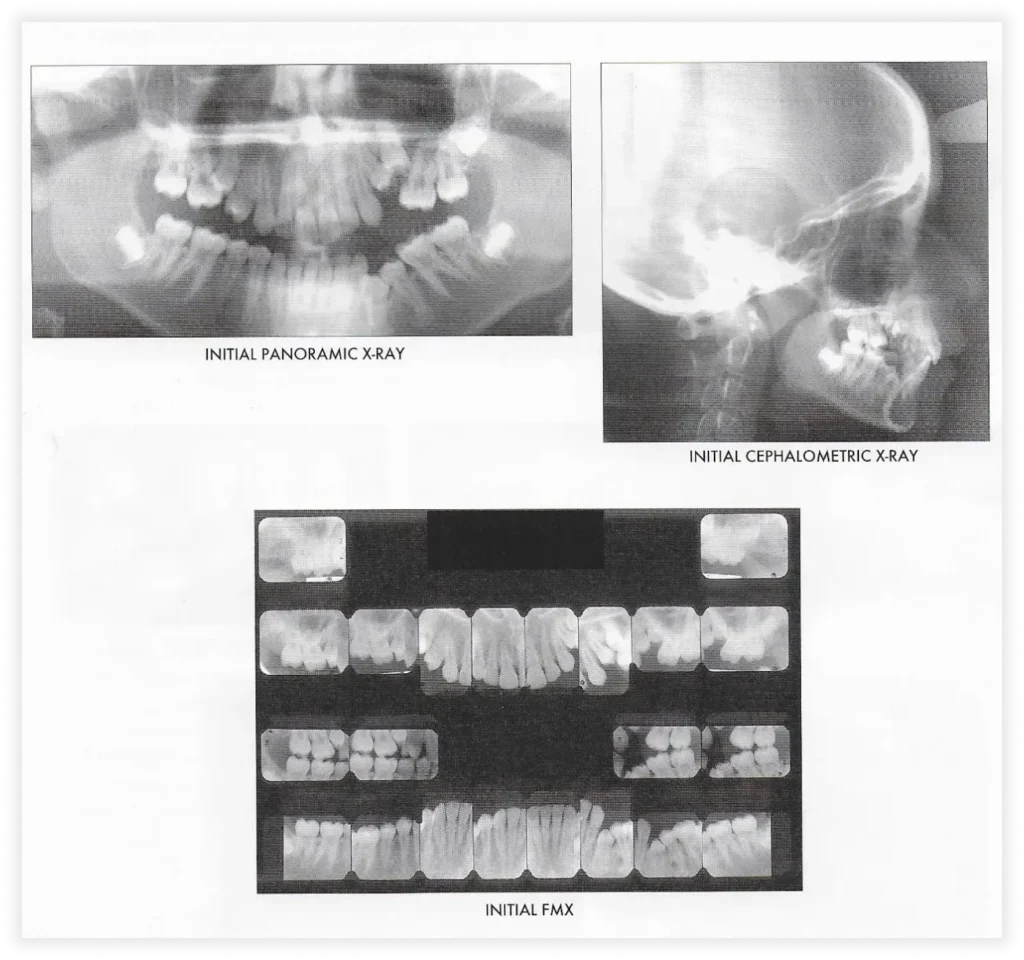

Take a look at some of our cases and successful transformations below.

Case #2

Initial Photos